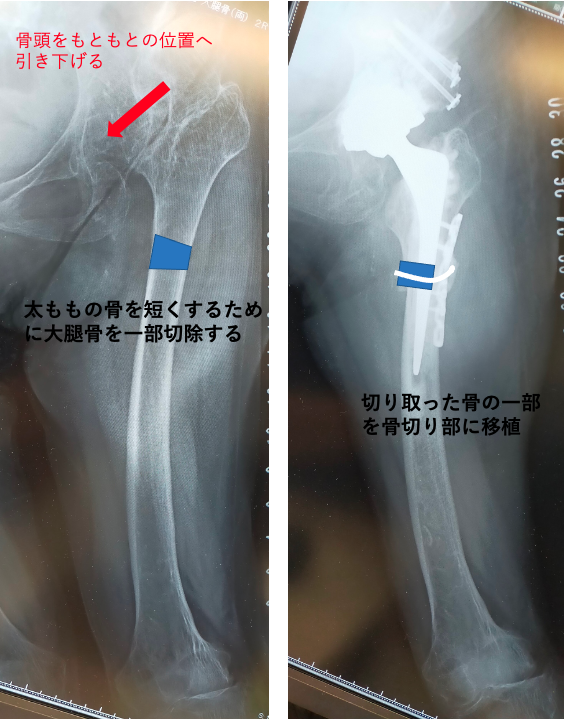

両側とも股関節は上外側に脱臼し、腸骨部に新たな関節が形成されています(二次臼蓋)。股関節の変形に伴い、関節の動きも大きく制限されており、左膝の関節症(X脚変形)も生じていました。左右の脚の長さに差が生じるために、骨盤は傾き、背骨も変形しています。

今回の症例では、まず左股関節症に対して大腿骨短縮骨切り併用THAを行いました。

正確な人工関節の設置が非常に難しいため、3Dテンプレートによる綿密な術前計画と、患者様ご本人の実物大の3D骨モデルを作成し、手術を行いました。

3Dテンプレートにより、3次元で評価することができるため、より適切な機種、設置位置などを再現することが可能です。

骨モデルで実際の人工関節の設置角度や骨欠損の状態をより正確に把握することができます。

無理に脚が引き伸ばされることで、神経や血管などに負担がかかり神経麻痺などを起こしてしまうため、大腿骨の長さを短く(短縮骨切り)することで、神経への負担を減らしました。

骨の欠損も著しく、自身の骨より採取した骨を移植(自家骨移植)し、人工関節の土台とします。

また骨粗鬆症も重度であり、人工関節の初期固定を良くするために、セメントを使用して人工関節を固定し、脱臼のリスクを減らすために脱臼抵抗性の高い機種(デュアルモビリティ)を使用するなどの様々な工夫が必要になります。